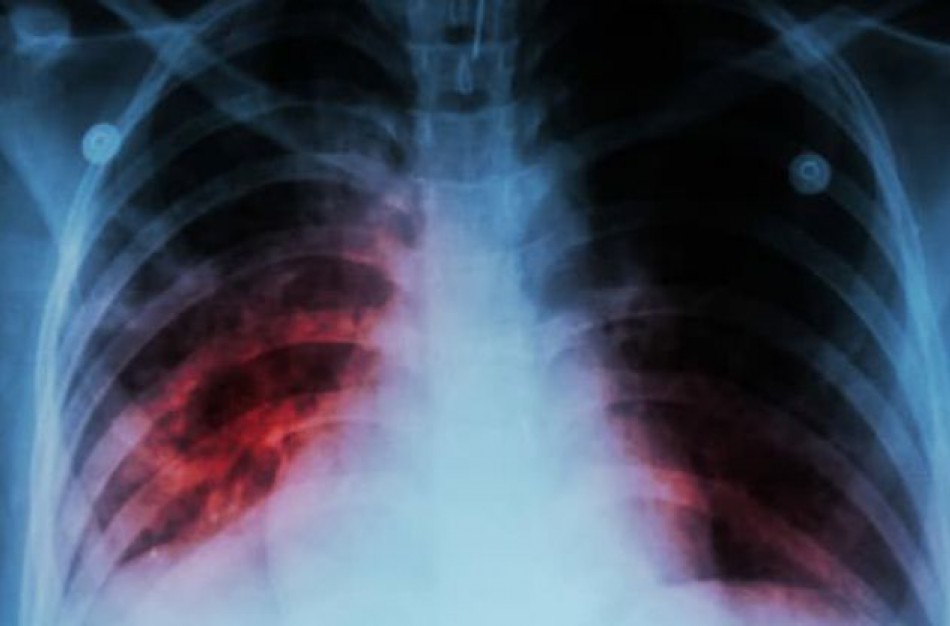

Tuberkuliozę sukelia bakterijos. Dažniausiai šios bakterijos atakuoja plaučius, tačiau taip pat gali paveikti inkstus, stuburą ar net smegenis.

Tuberkuliozė yra labai pavojinga infekcinė liga, nors daugelis sergančiųjų serga latentine šios ligos forma, tačiau apie 10 procentų visų sergančiųjų ši infekciją progresuoja į aktyvią tuberkuliozę, kuri negydoma gali pražudyti žmogų. Kvėpavimo organų tuberkuliozę sukelia bakterija, kuri plinta per orą. Pagrindinis šių bakterijų šaltinis yra žmogus sergantis atvira plaučių tuberkulioze. Didžiausią riziką užsikrėsti tuberkulioze, turi artimai ir ilgą laiką bendraujantys su atvira tuberkulioze sergančiais asmenimis asmenys.